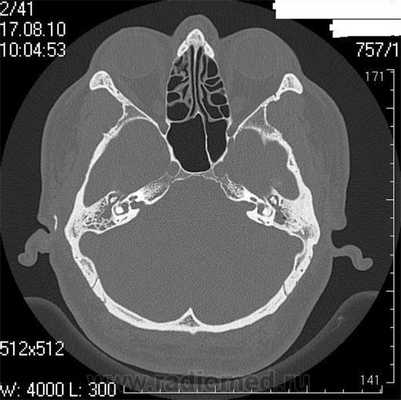

Что покажет КТ височных костей

Во время КТ получают послойные снимки височной кости и окружающих тканей в трех плоскостях. Толщина среза составляет всего несколько миллиметров, что позволяет врачу-рентгенологу рассмотреть не только все анатомические образования, но и минимальные патологические изменения.

На полученных снимках хорошо видны следующие структуры:

пирамида височной кости;

ячейки и антрум сосцевидного отростка;

улитка, преддверие, передний и задний полукружный каналы;

слуховые косточки среднего уха;

стенки наружного слухового прохода;

![Снимок (томограмма) височных костей в осевой проекции]()

Снимок (томограмма) височных костей в осевой проекции